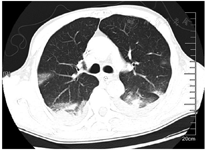

患者入院后立即予面罩吸氧、置胃管,甘露醇125 ml联合25%硫酸镁20 ml(每8小时1次)导泻;入院后12 h内予纯牛奶2 000 ml胃管内分次注入后,重复负压抽吸胃液;分别于7月6日0:15、12:50行血液灌流2 h,同时予甲强龙60 mg(每12小时1次)静脉滴注减轻肺水肿和渗出以及抗感染(哌拉西林钠/他唑巴坦4.5 g,每8小时1次),异甘草酸镁0.2 g静脉滴注1次/d保肝,泮托拉唑40 mg静脉滴注1次/d抑酸等对症支持治疗。入院当天患者发热,体温37.9 ℃、血氧饱和度下降至85%,予经口气管插管、呼吸机辅助呼吸、镇痛镇静治疗,患者气道内吸出黄白黏液样痰,复测P/F 255 mmHg[呼气末正压(PEEP)5 cmH2O]。入院后第2天予鼻饲肠内营养混悬液(SP)20 ml/h。入院后第4天肠内营养加量至50 ml/h,P/F下降至149 mmHg(PEEP 8 cmH2O);行气管镜检查示气道充血、水肿,部分气道黏膜坏死、剥脱;肺泡灌洗液培养示铜绿假单胞菌,予限制性液体管理。入院后第5天行经皮气管切开术,逐步撤离镇痛镇静药物,患者口唇破溃伴糜烂,予苏打水清洁口腔;行胸部CT检查示两肺多发渗出,考虑吸入性肺炎、双侧胸腔积液、腹腔积液(图1)。入院后第6天甲强龙减量为60 mg 1次/d,并加用低分子肝素4 000 IU预防深静脉血栓形成和肺微小血栓形成。入院后第10天停用甲强龙,后继续抗感染、全肠内营养支持、气管镜吸痰、肺保护性通气、肺复张及对症支持治疗。入院后第11天患者P/F上升至210 mmHg,胸部CT示两肺渗出较前明显吸收(图2)。

两肺渗出明显吸收